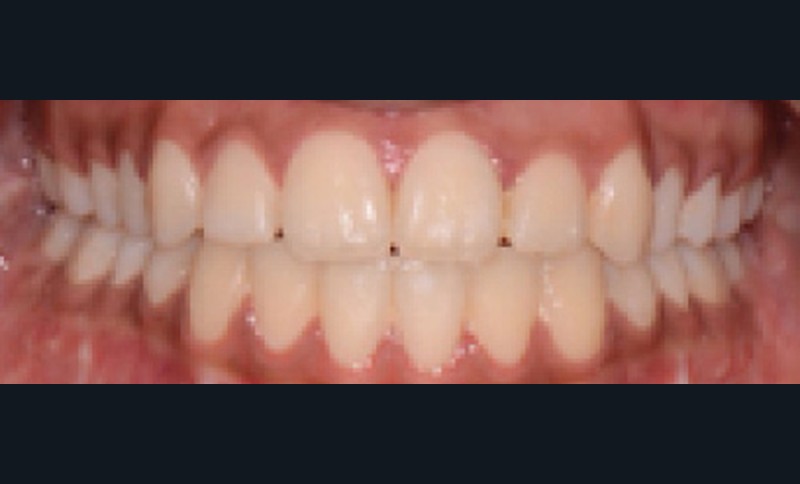

Sur le plan dentaire, elle présente une classe II d’Angle complète, une supraclusion de 4 mm et un surplomb de 6 mm ne correspondant pas au décalage de classe II molaire.

Nous avons pu repositionner l’incisive mandibulaire de 8° (fig. 10), obtenir un surplomb correspondant à la classe II d’Angle et ainsi réaliser l’avancée mandibulaire. Le chirurgien accompagne celle-ci d’une génioplastie afin d’harmoniser le profil. Nous corrigeons la DDD par stripping des incisives mandibulaires ce qui permet de corriger encore de 1° l’axe incisif.

Le résultat de fin de traitement est satisfaisant. Le profil de la patiente est harmonisé. Une contention fixe mandibulaire et maxillaire de canine à canine est choisie.